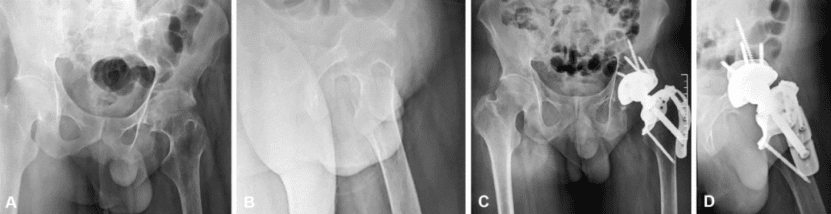

1) Total hip arthroplasty for severe osteoporosis of the proximal femur

For patients with severe proximal femoral osteoporosis who need artificial hip replacement due to severe pain and severe mobility impairment, the bio-fixed femoral stem has subsidence and rotational instability, and cannot obtain immediate stability; It is unavoidable that the interface between the cement and the bone marrow cavity will loosen and fail in the medium and long term. The author designed and 3D printed a structure that fits the shape and the surface is porous, which can not only achieve instant stability, but also facilitate bone ingrowth and integration. According to the principle of biomechanics, the individualized stress-free joint and serial osteotomy, drilling, and surgical guide plate installation for permanent biological fixation can be obtained, and the artificial hip joint replacement operation was successfully performed for this patient. After two years of follow-up, the patient’s pain was relieved, activity function was significantly improved, and the prosthesis did not loosen.